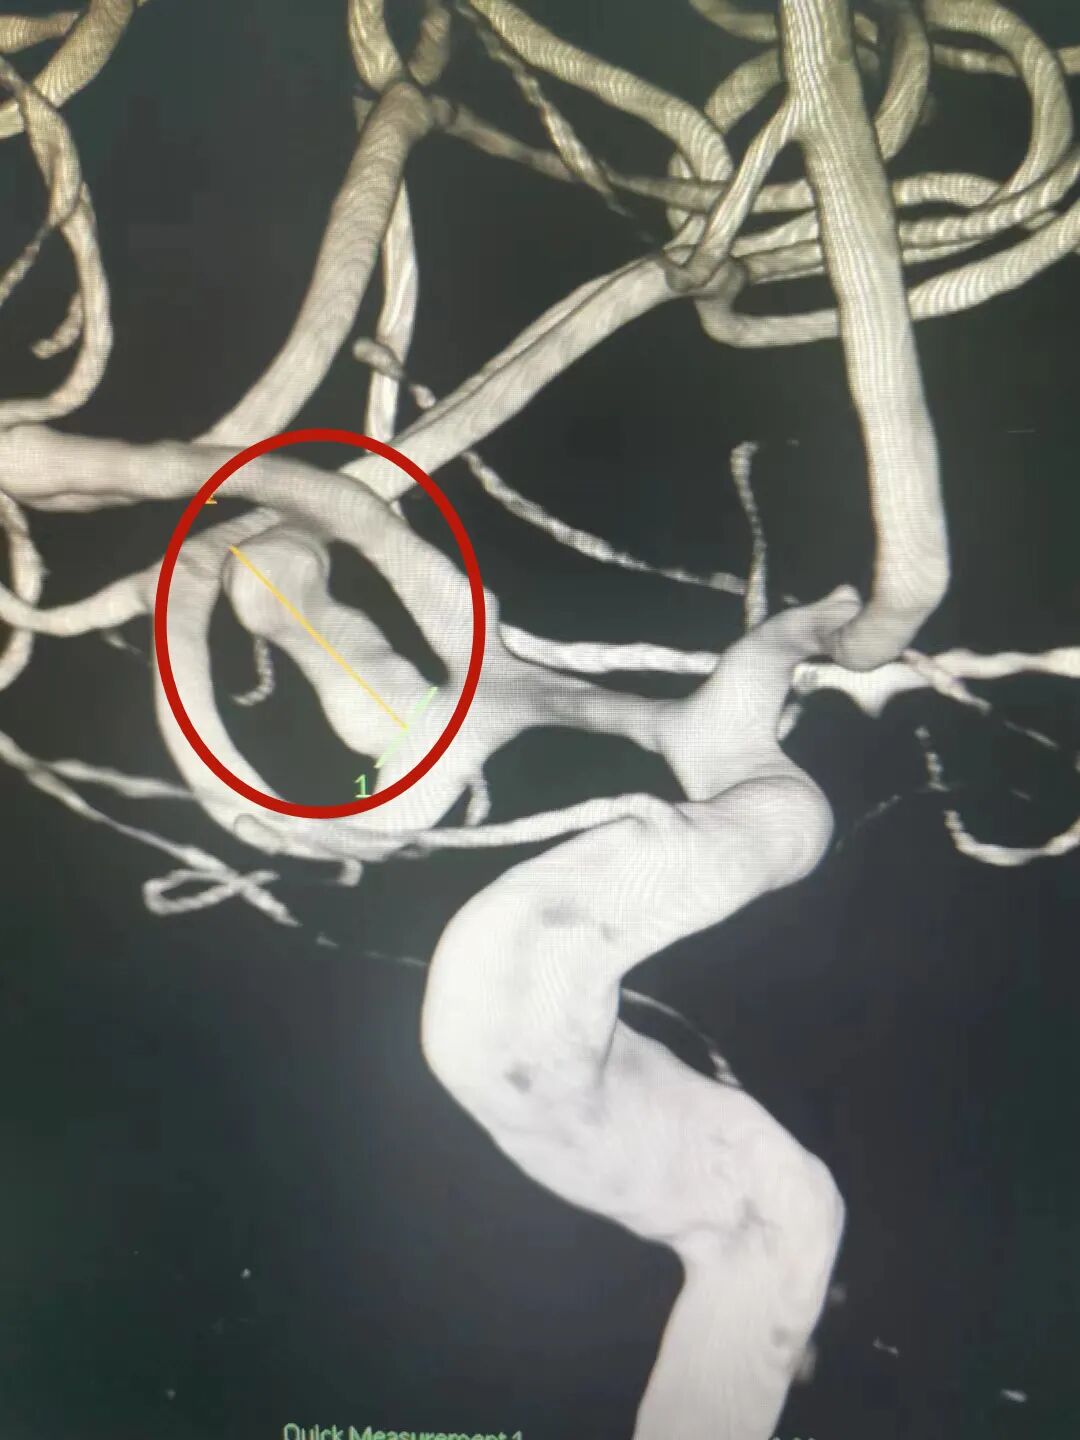

5月15日家是江苏省的何某在刘寨打工时突发疾病,通过急救车收住中康医院神经内科一病区,查头颅CT显示,脑部有动脉瘤

图片

脑动脉瘤如同脑子里的“定时炸弹”,如果发生“爆破”,后果就不堪设想,不仅会导致剧烈头痛、恶心、视物模糊、意识昏迷,严重时甚至威胁生命!